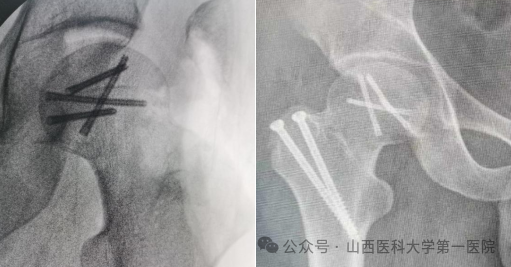

精确解剖复位后2.5空心埋头钉固定,复位股骨头脱位及大转子截骨块